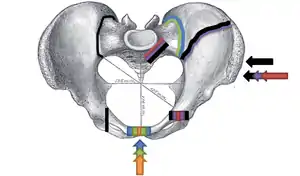

The Young-Burgess classification system is based on mechanism of injury: anteroposterior compression type I, II and III, lateral compression types I, II and III, and vertical shear,[5] or a combination of forces.

Lateral compression (LC) fractures involve transverse fractures of the pubic rami, either ipsilateral or contralateral to a posterior injury.

- Grade I – Associated sacral compression on side of impact

- Grade II – Associated posterior iliac ("crescent") fracture on side of impact

- Grade III – Associated contralateral sacroiliac joint injury

The most common force type, lateral compression (LC) forces, from side-impact automobile accidents and pedestrian injuries, can result in an internal rotation.[9] The superior and inferior pubic rami may fracture anteriorly, for example. Injuries from shear forces, like falls from above, can result in disruption of ligaments or bones. When multiple forces occur, it is called combined mechanical injury (CMI). The best imaging modality to use for this classification is probably a pelvic CT scan.

Open book fracture

One specific kind of pelvic fracture is known as an 'open book' fracture. This is often the result from a heavy impact to the groin (pubis), a common motorcycling accident injury. In this kind of injury, the left and right halves of the pelvis are separated at front and rear, the front opening more than the rear, i.e. like an open book that falls to the ground and splits in the middle. Depending on the severity, this may require surgical reconstruction before rehabilitation.[10] Forces from an anterior or posterior direction, like head-on car accidents, usually cause external rotation of the hemipelvis, an “open-book” injury. Open fractures have increased risk of infection and hemorrhaging from vessel injury, leading to higher mortality.[11]